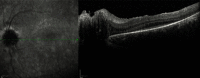

A case of a patient with the Alström syndrome (AS) that was misdiagnosed as Leber's hereditary optic neuropathy or retinitis pigmentosa for 13 years is presented. AS is a rare genetic disorder caused by mutations in the ALMS1 gene. AS may lead to abnormal ciliary formation and function. AS affects metabolism, and symptomatology includes type 2 diabetes mellitus (T2DM), obesity, hypogonadism and gynecomastia in males, progressive bilateral sensorineural hearing loss, cardiomyopathy, nonalcoholic fatty liver disease (NAFLD), cirrhosis, and chronic progressive kidney disease. The onset of the above symptoms may vary significantly. The ophthalmic manifestation is early onset cone-rod dystrophy that starts as progressive vision loss, photophobia, and nystagmus in the first months of life. An accurate diagnosis may enable specialists to facilitate a significantly positive effect in the everyday life of a patient. Genetic counseling may also be recommended for these patients. Diagnosis was confirmed by DNA testing, thus highlighting its necessity in everyday practice.